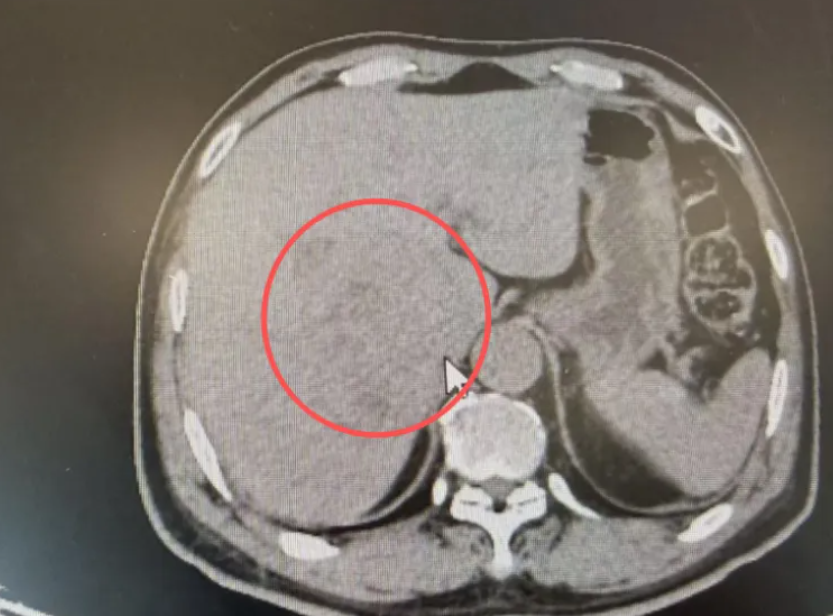

手术后的张先生(化名),终于露出了久违的笑容。几个月前,他面对的是一个令人绝望的诊断——直径约 10 公分的巨块型肝癌,而且肿瘤像树根一样紧紧缠绕着门静脉主干,几乎没有安全的分离空间。在多数医院,这类病例往往被认为“无法安全手术”。但在和祐医院肝普外科胆外科团队手中,这颗“体内炸弹”被成功拆除。